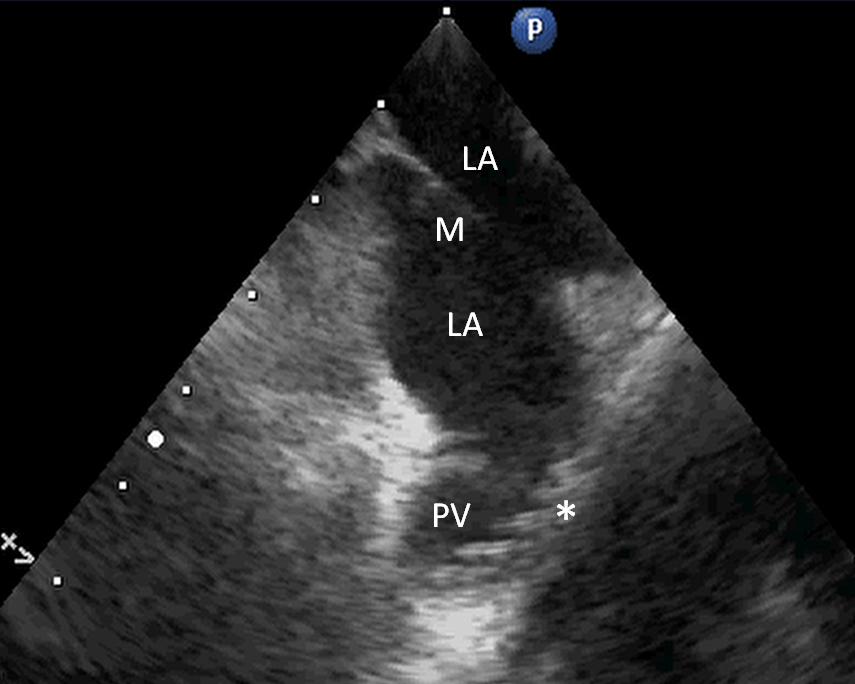

Fig. 2. ICE image during procedure. LA: left atrium. M: additional membrane. PV: right pulmonary vein. *: multipolar mapping catheter.

Transseptal punction was done in a standard manner utilizing intracardiac echocardiography (ICE), accessing the interatrial septum in a distance to the additional membrane. ICE clearly visualized the additional membrane (Fig. 2). Mapping was done using an atraumatic 18polar high-density mapping catheter (Abbott HD Grid ®) to avoid potential trauma. The right pulmonary veins could be accessed through the inferior opening of the membrane. It was feasible to visualize the membrane itself via the 3D system (Fig. 3). PVI was done in a standard manner using radiofrequency ablation by an irrigated tip catheter with contact force registration.